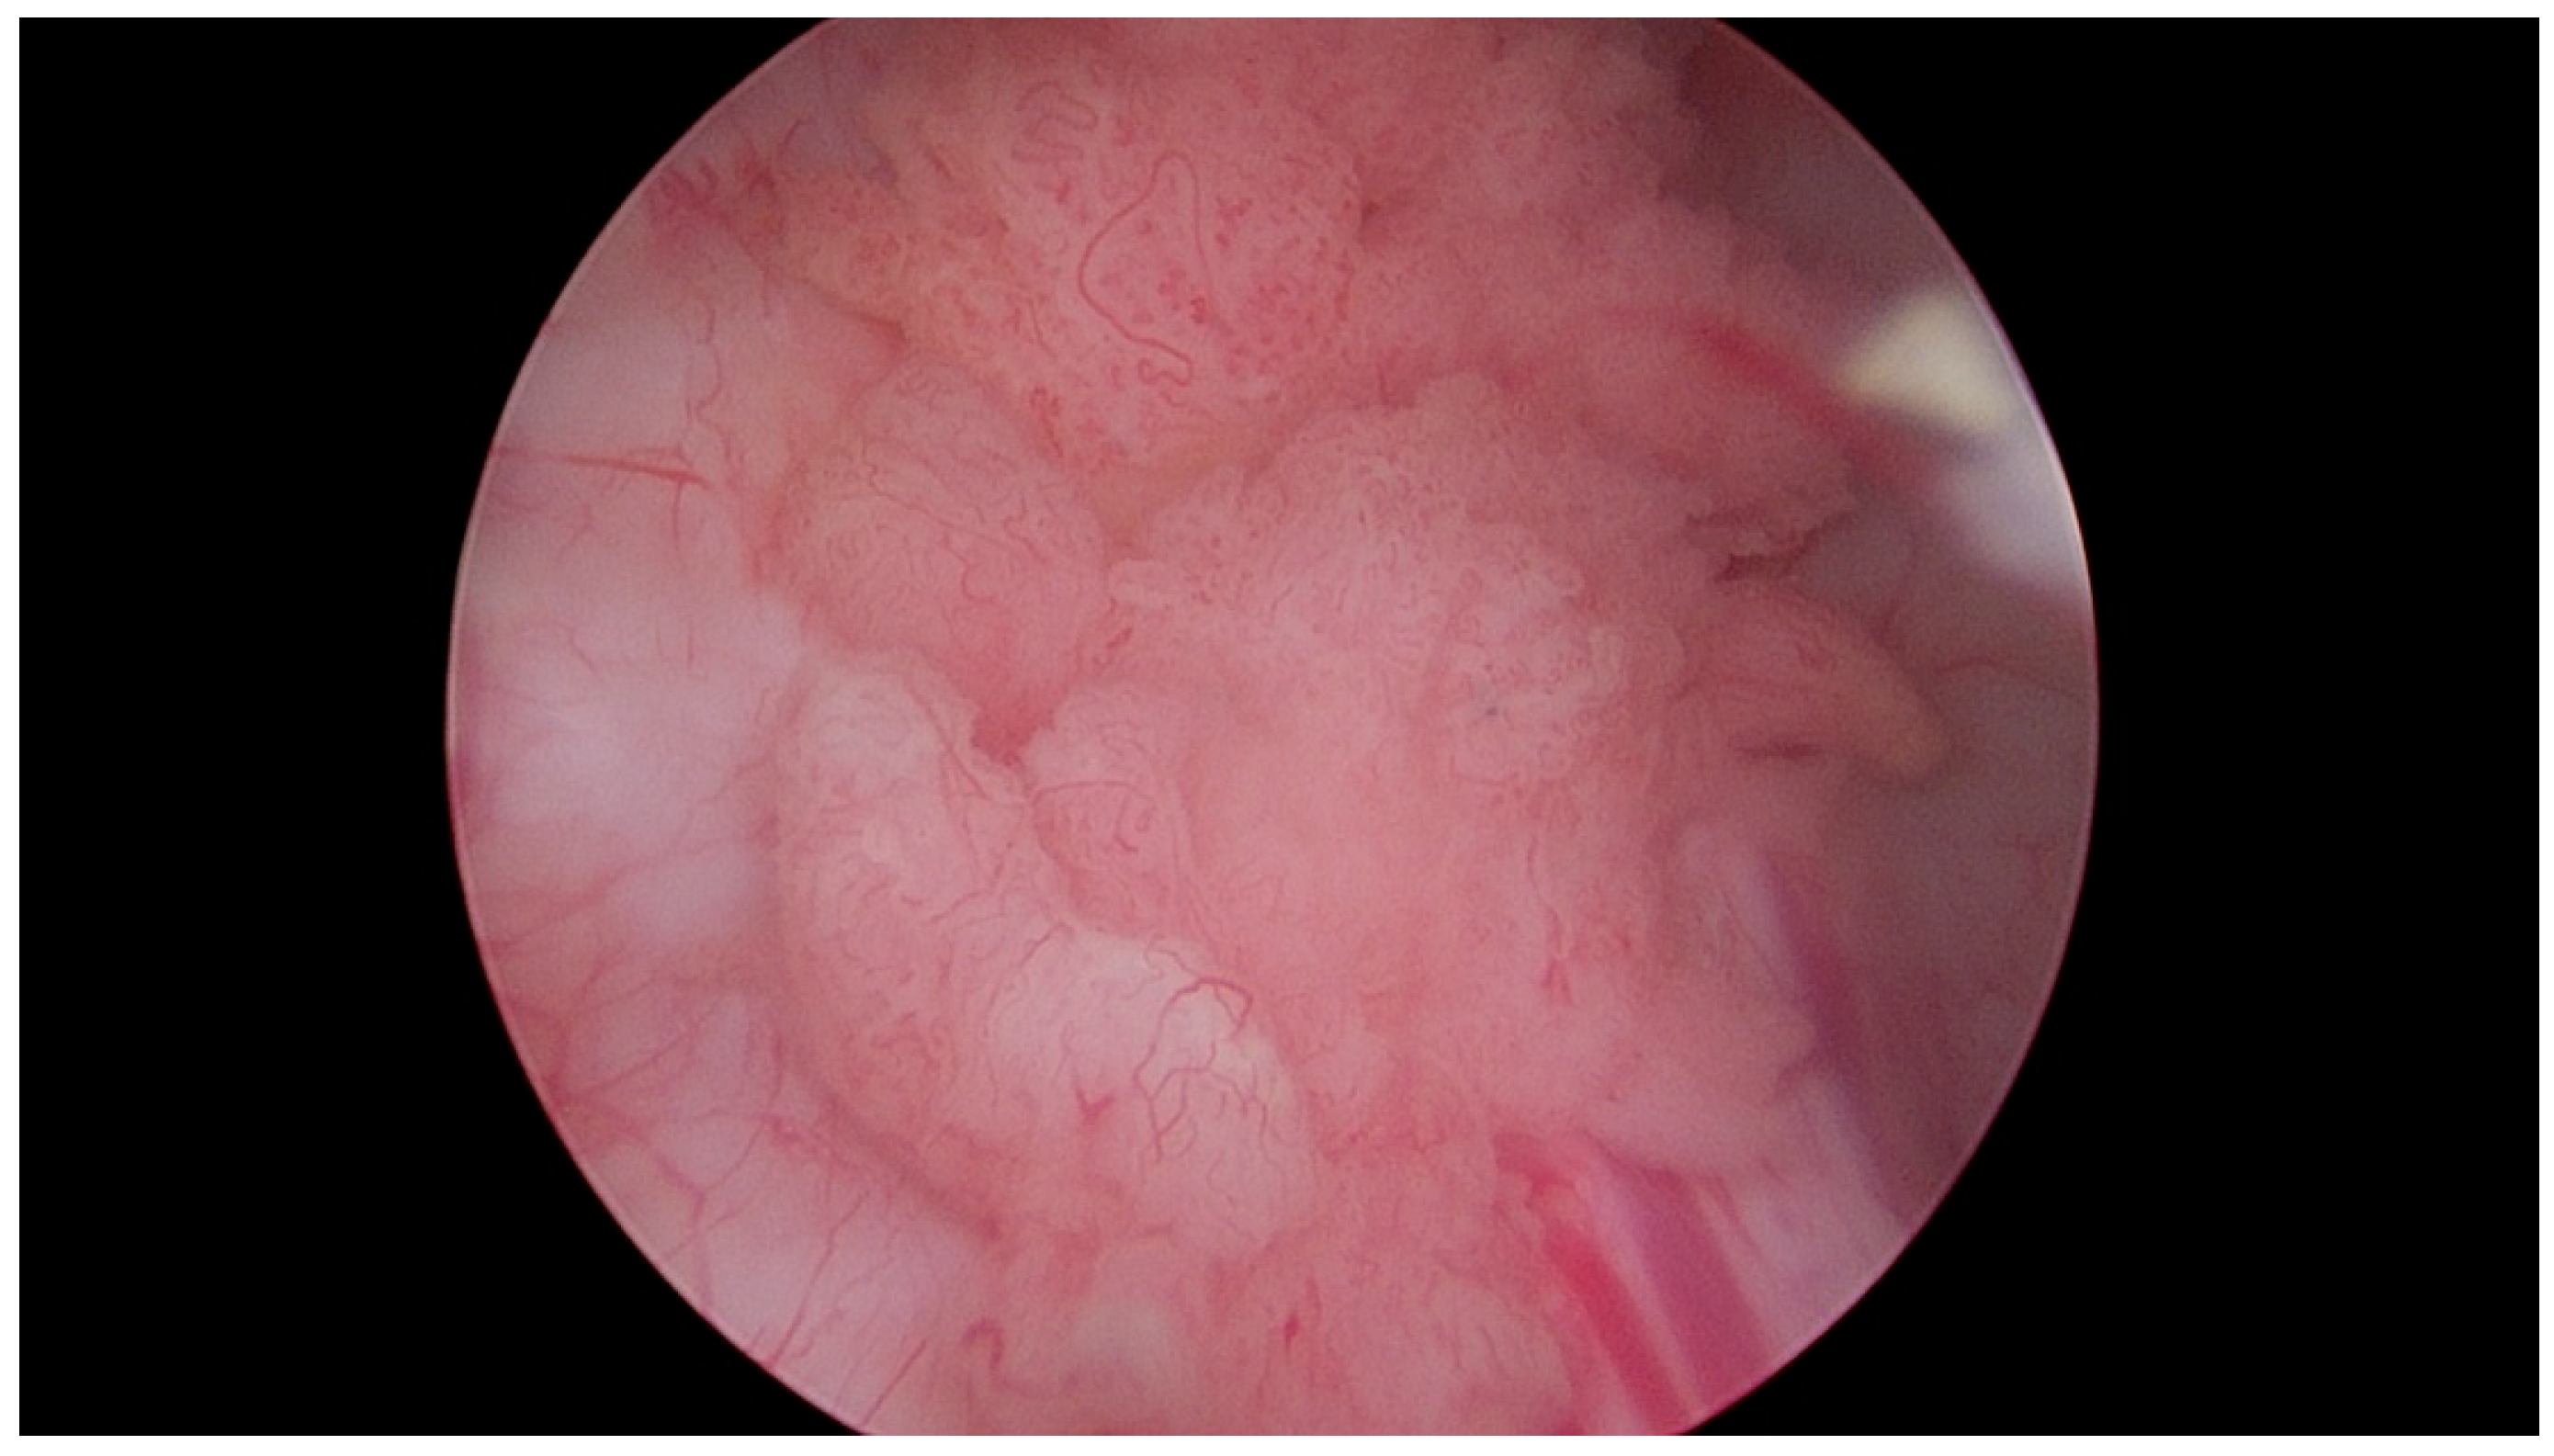

Figure 3.

Papillary urothelial carcinoma of the urinary bladder. Own study based on Ethical Approval of the University of Rzeszow, No. 29/05/2019. Titled 12. 2019, Evaluation of the efficacy of the in vitro photodynamic method in superficial bladder cancer, by M.D. Dominik Godlewski.

Figure 4.

Papillary urothelial carcinoma of the urinary bladder—visible pathological vascularization within the exophytic part of the tumor, as well as at its base. Own study based on Ethical Approval of the University of Rzeszow, No. 29/05/2019. Titled 12. 2019, Evaluation of the efficacy of the in vitro photodynamic method in superficial bladder cancer, by M.D. Dominik Godlewski.